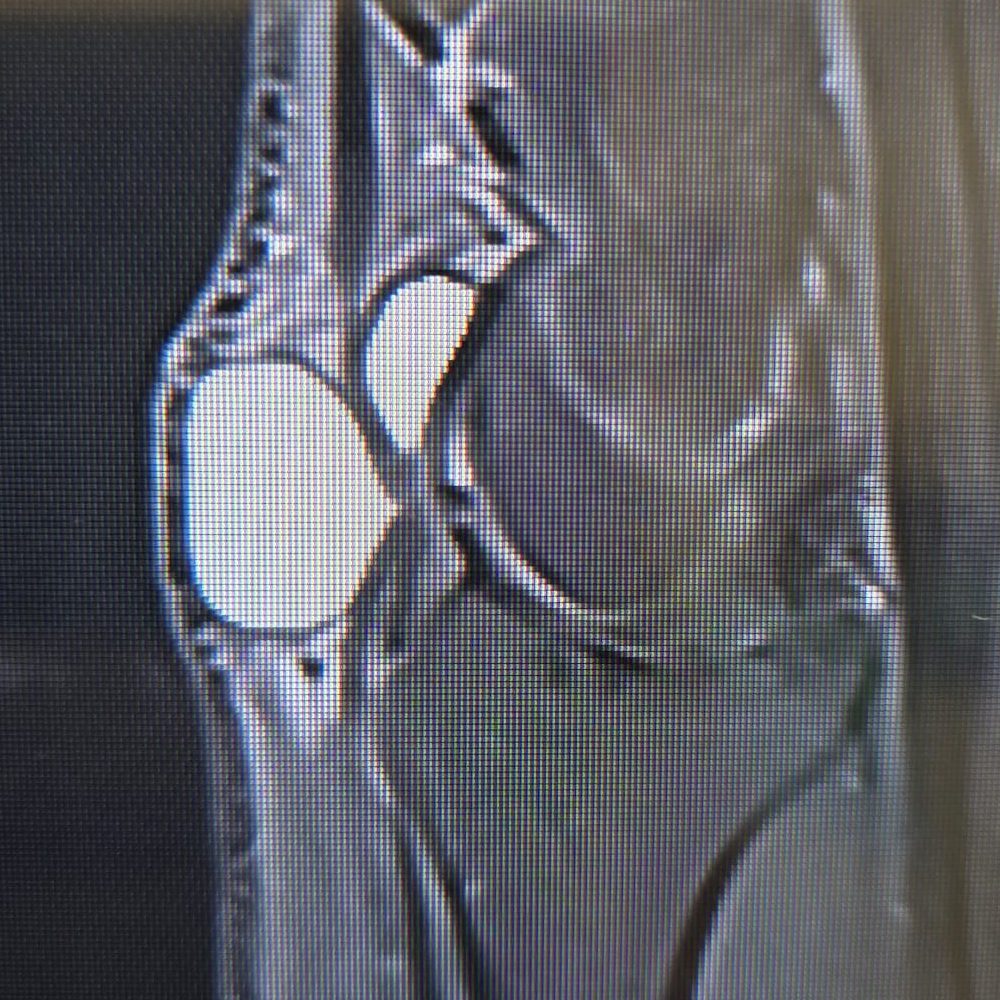

- Ultrason: Kistin iç yapısı, sıvı dolu olup olmadığı, damar yapılarıyla ilişkisi netleşir.

- Manyetik Rezonans (MR): Küçük ve gizli kistlerde detaylı görüntü sağlar.